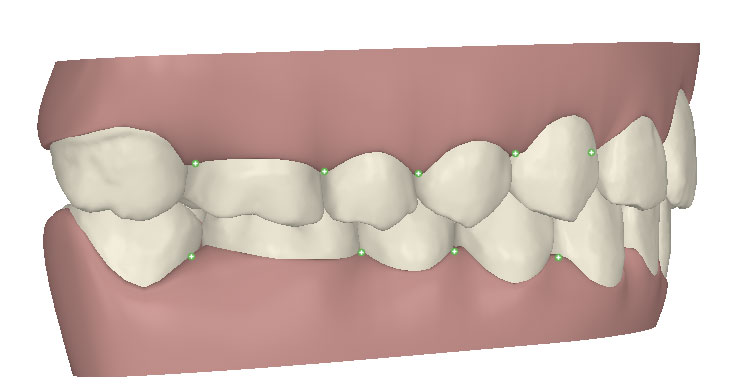

コンピューターを使って作製した透明なマウスピース型の矯正装置(アライナー)を段階的につけ替えていき、それにより歯列を矯正し、歯並びへと改善します。はじめに 治療開始から終了までのアライナーができあがってきます。マウスピース型矯正装置(インビザライン)の最大の特徴として「クリンチェック」というソフトがあります。3D のコンピュータ シュミレーション画像で、治療開始から完了までを目で見て確認することができます。

マウスピース型矯正装置(インビザライン)治療においては、クリンチェックというシミュレーションソフトを活用しております。

このクリンチェックの魅力は、治療前の現在の歯並びから治療後の歯並びを視覚化して患者様にご説明できる点にあります。

また、抜歯・非抜歯、全体矯正・部分矯正などそれぞれの治療パターンをシミュレーションすることが可能です。